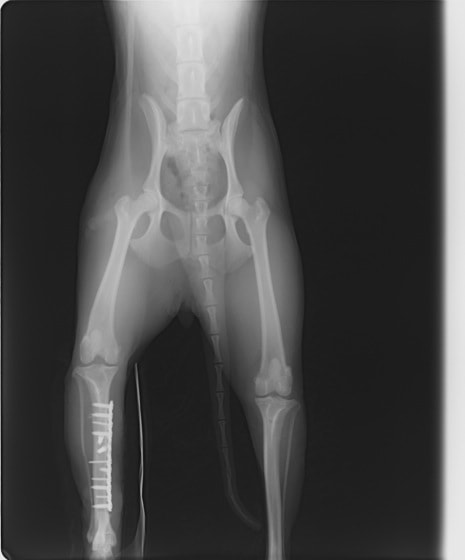

ペルシャ猫 11ヶ月齢 雄

他院にて左大腿骨遠位の成長板骨折(salter-harrisⅠ型)が認められており、治療相談を目的として来院。当院にて、キルシュナーワイヤーを用いたピンニングにより骨折部位の整復を行いました。術後の経過は良好で、現在も経過観察中です。

術後レントゲン

Arthrex社のターゲティングデバイスを用いてピンニングの位置を調整することで、確実な固定を行っています。当院ではこの手術器具以外にも、人の手術にも使用される様々な器具を導入し、手術精度を高め、また医療メーカーと新しい器具の開発、試作にも取り組んでおります。